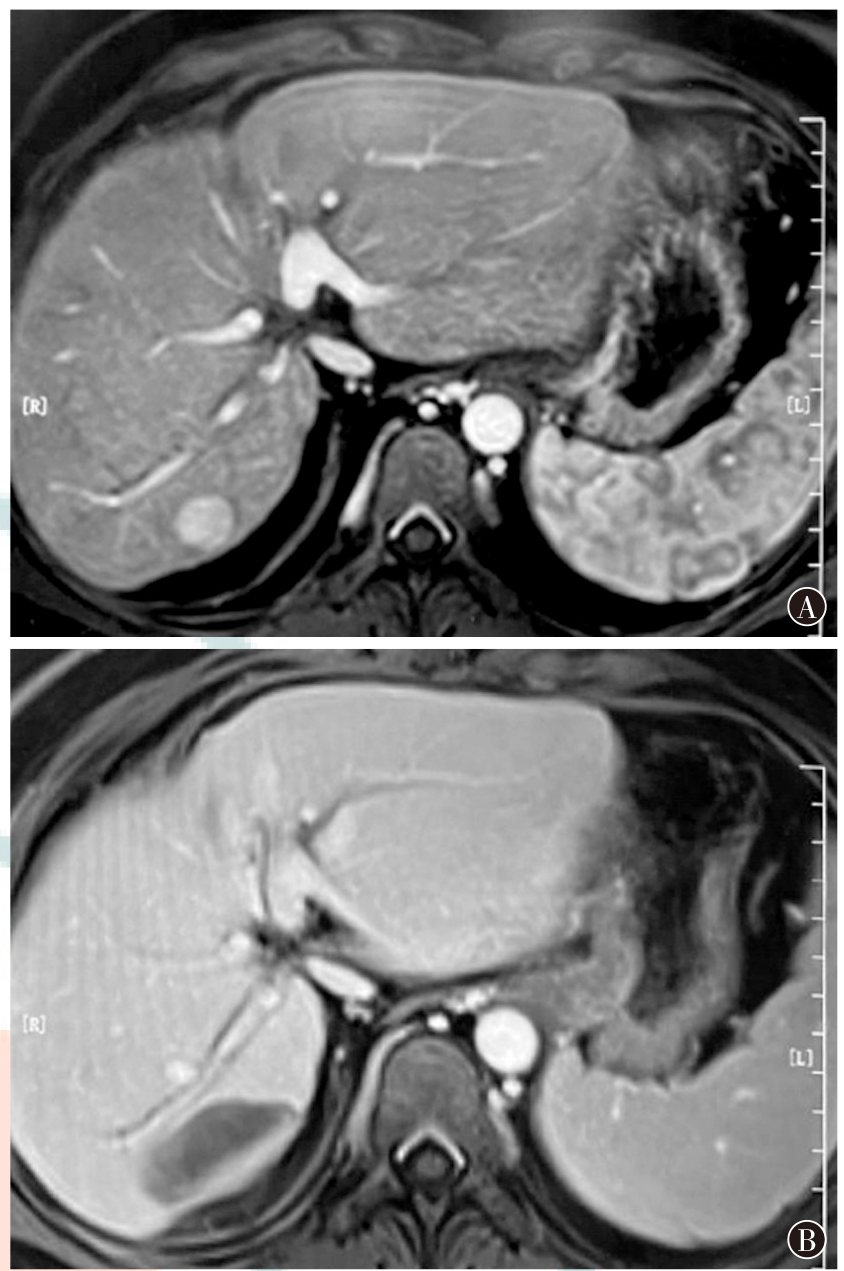

目的探究血清基质金属蛋白酶-9(MMP-9)、脂肪酸结合蛋白质5(FABP5)联合MRI对原发性肝癌经皮穿刺射频消融术后疗效及复发的预测价值。方法选择2022年6月至2023年5月于空军军医大学第一附属医院行经皮穿刺射频消融术治疗的192例原发性肝癌患者作为研究对象。术前一周内行MRI检查并记录表观扩散系数(ADC)值;采用酶联免疫吸附法测定血清MMP-9、FABP5的水平。根据MRI检查判断病灶消融情况,将患者分为完全消融组(n=157)和病灶残留组(n=35);对病灶完全消融患者定期随访1年,记录其复发情况,根据患者复发情况,将患者分为未复发组(n=115)和复发组(n=42)。比较完全消融组与病灶残留组、未复发组与复发组患者MMP-9、FABP5水平以及ADC值。采用受试者操作特征(ROC)曲线评估血清MMP-9、FABP5联合MRI对患者术后疗效和复发的预测价值。结果完全消融组患者血清MMP-9、FABP5水平、ADC值分别为(181.05±29.68)ng/ml、(7.95±1.82)μg/L、(1.32±0.45)×10-3mm2/s,病灶残留组分别为(202.18±35.06)ng/ml、(9.56±2.39)μg/L、(0.75±0.23)×10-3mm2/s,完全消融组MMP-9、FABP5水平均明显低于病灶残留组,ADC值明显高于病灶残留组,差异均有统计学意义(t=3.68,P<0.001;t=4.45,P<0.001;t=7.27,P<0.001)。血清MMP-9、FABP5、ADC值单独预测患者术后疗效的曲线下面积(AUC)分别为0.68(95%CI为0.61~0.75)、0.75(95%CI为0.68~0.81)和0.90(95%CI为0.85~0.94),三者联合预测的AUC为0.94(95%CI为0.89~0.97),三者联合优于MMP-9、FABP5、ADC值各自单独预测(Z=5.72,P<0.001;Z=4.84,P<0.001;Z=2.29,P=0.022)。未复发组患者血清MMP-9、FABP5水平、ADC值分别为(176.52±30.28)ng/ml、(8.69±1.92)μg/L、(1.35±0.29)×10-3mm2/s,复发组分别为(201.85±28.72)ng/ml、(11.05±2.86)μg/L、(1.14±0.12)×10-3mm2/s,未复发组患者血清MMP-9、FABP5水平均明显低于复发组,ADC值明显高于复发组,差异均有统计学意义(t=4.70,P<0.001;t=5.93,P<0.001;t=4.55,P<0.001)。血清MMP-9、FABP5、ADC值单独预测患者术后复发的AUC分别为0.74(95%CI为0.66~0.81)、0.90(95%CI为0.84~0.94)和0.74(95%CI为0.66~0.80),三者联合预测的AUC为0.95(95%CI为0.90~0.98),三者联合优于MMP-9、FABP5、ADC值各自单独预测(Z=5.00,P<0.001;Z=3.03,P=0.002;Z=5.33,P<0.001)。结论完全消融组经皮穿刺射频消融术治疗后原发性肝癌患者血清MMP-9、FABP5水平均明显低于病灶残留组,ADC值明显高于病灶残留组,未复发组患者血清MMP-9、FABP5水平亦明显低于复发组,ADC值亦明显高于复发组。血清MMP-9、FABP5联合MRI检测对肝癌经皮穿刺射频消融术后疗效和复发情况的预测具有较高的临床价值。

ObjectiveTo investigate the predictive value of serum matrix metalloproteinase-9 (MMP-9), fatty acid-binding protein 5 (FABP5) combined with MRI for the efficacy and recurrence of primary liver cancer after percutaneous radiofrequency ablation.MethodsA total of 192 patients with primary liver cancer who underwent percutaneous radiofrequency ablation treatment at the First Affiliated Hospital of Air Force Medical University from June 2022 to May 2023 were selected as the research subjects. MRI examination was performed within one week before the treatment, and the apparent diffusion coefficient (ADC) value was recorded. The enzyme-linked immunosorbent assay (ELISA) was used to determine the levels of MMP-9 and FABP5 in the serum. According to the results of MRI examination, the ablation status of the lesions was determined, and the patients were divided into a complete ablation group (n=157) and a residual lesion group (n=35). Patients with completely ablated lesions were regularly followed up for one year, and their recurrence status was recorded. According to the recurrence of the patients, the patients were divided into a non-recurrence group (n=115) and a recurrence group (n=42). The levels of MMP-9 and FABP5 and the ADC values of the patients in the complete ablation group and the residual lesion group, as well as those in the non-recurrence group and the recurrence group, were compared. The receiver operator characteristic (ROC) curve was used to evaluate the predictive value of serum MMP-9 and FABP5 combined with MRI for the postoperative efficacy and recurrence of the patients.ResultsThe levels of serum MMP-9 and FABP5, and the ADC value of patients in the complete ablation group were (181.05±29.68) ng/ml, (7.95±1.82) μg/L, and (1.32±0.45)×10-3mm²/s, respectively, while those in the residual lesion group were (202.18±35.06) ng/ml, (9.56±2.39) μg/L, and (0.75±0.23)×10-3mm²/s, respectively. The levels of MMP-9 and FABP5 in the complete ablation group were significantly lower than those in the residual lesion group, and the ADC value was significantly higher than that in the residual lesion group, with statistically significant differences (t=3.68,P<0.001;t=4.45,P<0.001;t=7.27,P<0.001). The areas under the curve (AUC) of serum MMP-9, FABP5, and ADC value alone in predicting the postoperative efficacy of patients were 0.68 (95%CI: 0.61-0.75), 0.75 (95%CI: 0.68-0.81), and 0.90 (95%CI: 0.85-0.94), respectively. The AUC of the combined prediction of these three was 0.94 (95%CI: 0.89-0.97), and the combined prediction of these three was superior to the individual prediction of MMP-9, FABP5, and ADC value (Z=5.72,P<0.001;Z=4.84,P<0.001;Z=2.29,P=0.022). The levels of serum MMP-9 and FABP5, and the ADC value of patients in the non-recurrence group were (176.52±30.28) ng/ml, (8.69±1.92) μg/L, and (1.35±0.29)×10-3mm²/s, respectively, while those in the recurrence group were (201.85±28.72) ng/ml, (11.05±2.86) μg/L, and (1.14±0.12)×10-3mm²/s, respectively. The levels of serum MMP-9 and FABP5 of patients in the non-recurrence group were significantly lower than those in the recurrence group, and the ADC value was significantly higher than that in the recurrence group, with statistically significant differences (t=4.70,P<0.001;t=5.93,P<0.001;t=4.55,P<0.001). The AUCs of serum MMP-9, FABP5, and ADC value alone in predicting the postoperative recurrence of patients were 0.74 (95%CI: 0.66-0.81), 0.90 (95%CI: 0.84-0.94), and 0.74 (95%CI: 0.66-0.80), respectively. The AUC of the combined prediction of these three was 0.95 (95%CI: 0.90-0.98), and the combined prediction of these three was superior to the individual prediction of MMP-9, FABP5, and ADC value (Z=5.00,P<0.001;Z=3.03,P=0.002;Z=5.33,P<0.001).ConclusionsThe levels of serum MMP-9 and FABP5 in patients with primary liver cancer treated by percutaneous radiofrequency ablation in the complete ablation group are significantly lower than those in the residual lesion group, and the ADC value is significantly higher than that in the residual lesion group. The levels of serum MMP-9 and FABP5 of patients in the non-recurrence group are also significantly lower than those in the recurrence group, and the ADC value is also significantly higher than that in the recurrence group. The combined detection of serum MMP-9, FABP5 and MRI has a relatively high clinical value in predicting the efficacy and recurrence of patients after percutaneous radiofrequency ablation for liver cancer.